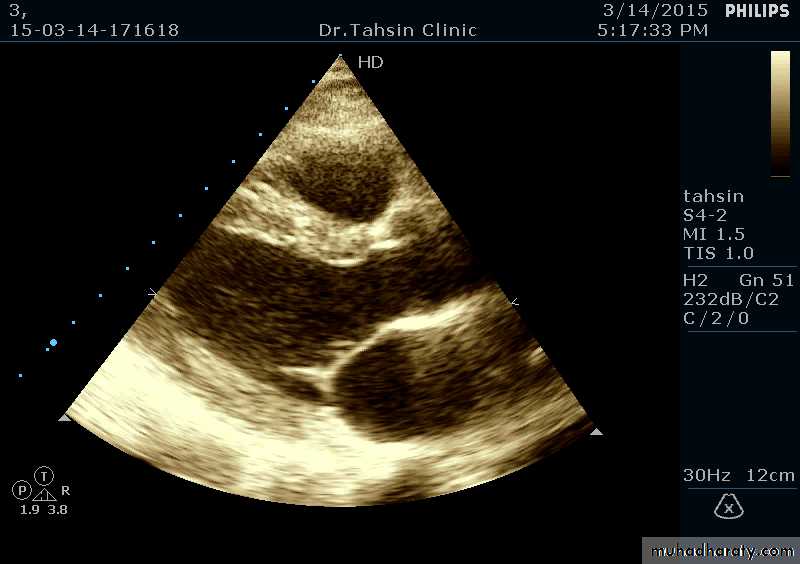

Two Dimensional Echocardiography

Ultrasound beam passing through the heart generates cross sectional images or “slices” of the heartVarious structures can be seen in real time

Two Dimensional Echocardiography indications

Assessment of LV functionDiagnosis & quantitation of severity of valvular lesions

Identification of vegetations

Identifying the source of systemic embolism

Detection of pericardial effusion